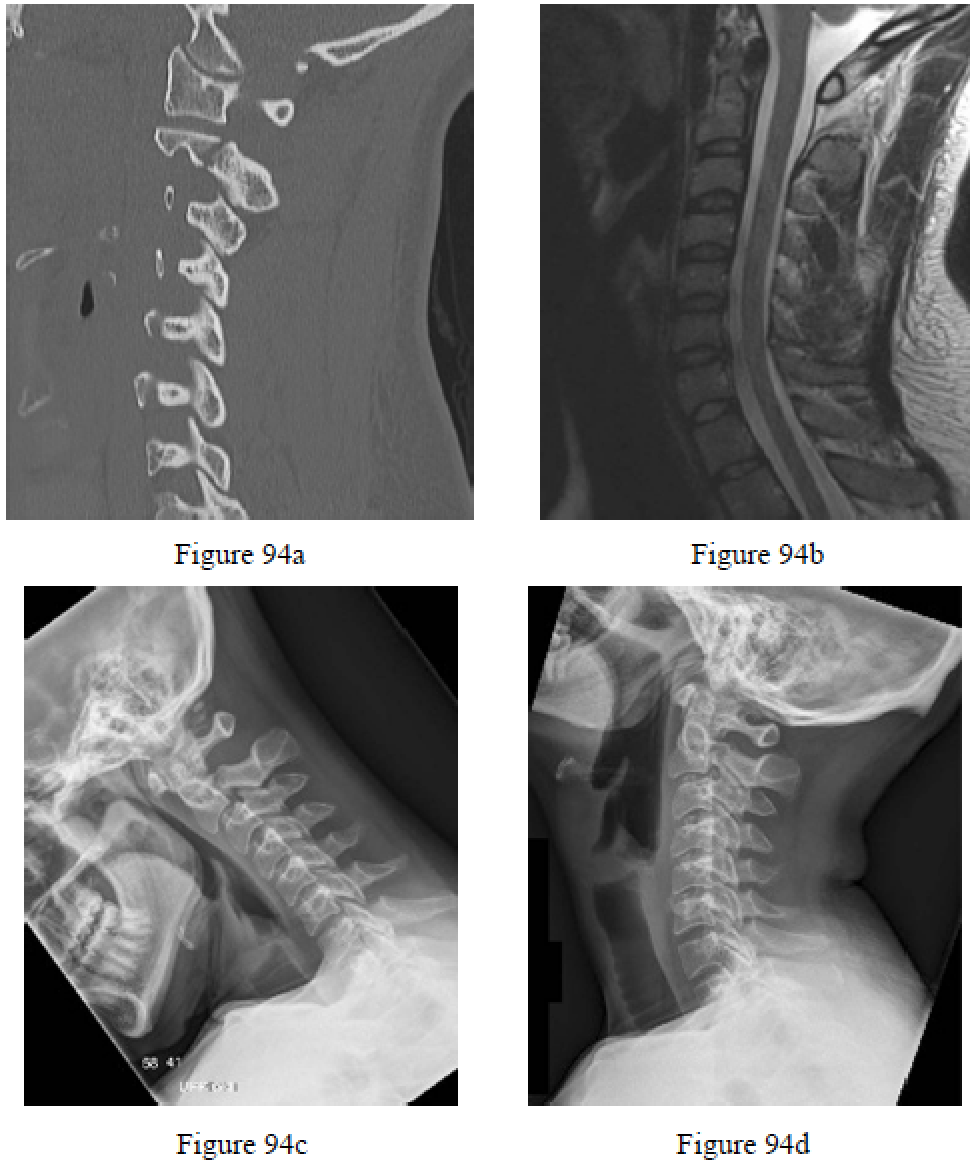

Question 94

Figures 94a and 94b are the sagittal CT and T2-weighted MRI cervical spine scans of a 25-year-old man who has neck pain after a motor vehicle collision. Examination reveals limited range of motion of the cervical spine and tenderness to palpation below the occiput, but his neurologic function is normal. Figures 94c and 94d are his flexion and extension lateral radiographs. What is the most appropriate treatment option?